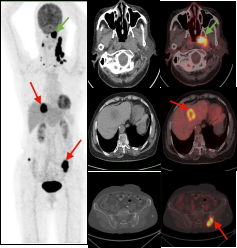

鼻咽癌全身转移:PET/CT显像示鼻咽左侧高代谢软组织肿块(绿色箭头);病理证实鼻咽非角化上皮癌,双侧颈部、肝脏及双侧髂骨多发转移瘤(红色箭头)。

胰腺癌全身转移:胰腺体尾部胰腺癌(绿色箭头),肝脏多发转移瘤及胸9椎体转移瘤(红色箭头)。

双癌检出:通过PET/CT一站式检查,同时检出两种肿瘤:甲状腺癌(绿色箭头)及子宫内膜癌(红色箭头),有利于临床治疗方案选择。